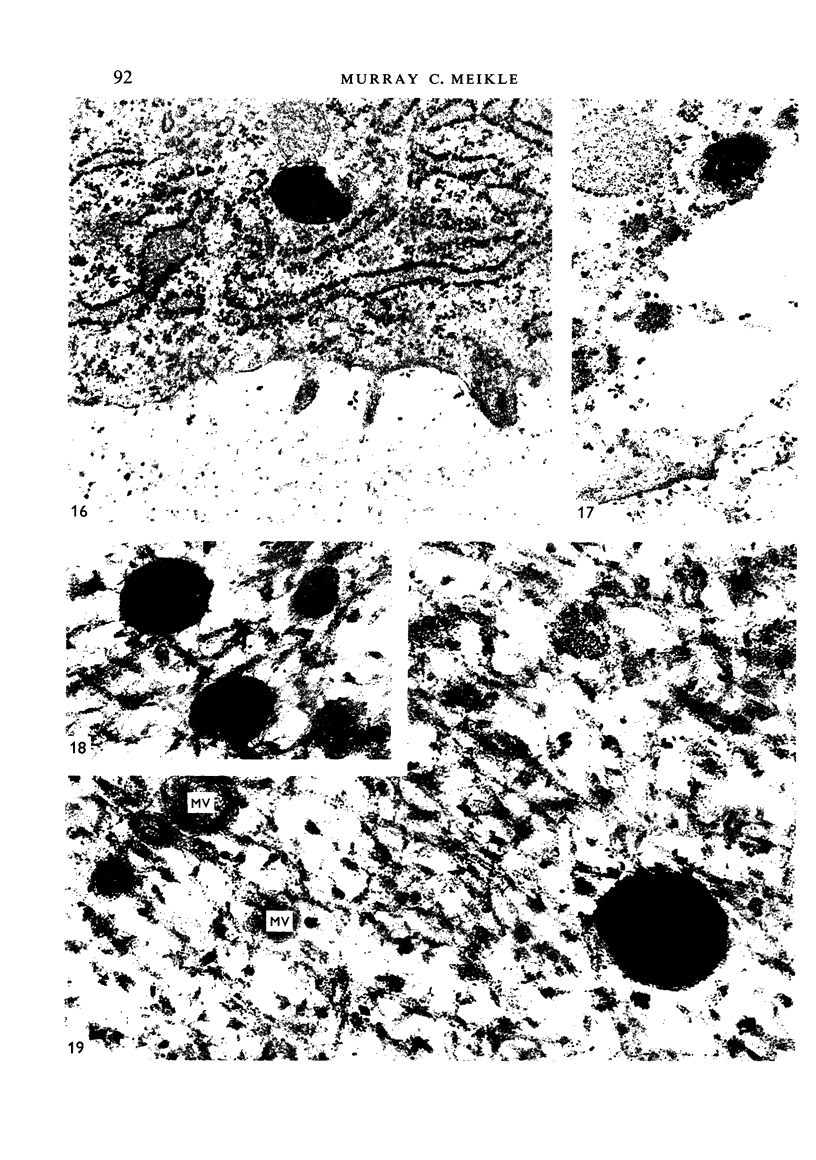

Using electron microscopic and histochemical methods it was possible to demonstrate in condylar cartilage the presence of acid phosphatase and aryl sulphatase in lysosome-like bodies of the cartilage cells, confirming that they are lysosomes. Lysosome-like bodies were also present in the extracellular matrix, but they reacted for acid phosphatase only. Lysosomes extruded by the cells may well provide a means whereby lysosomal enzymes are enabled to take part in the preliminaries to matrix calcification. The large numbers of lysosomes in the hypertrophic chondrocytes, however, are probably more concerned in bringing about autolysis of the cells than in promoting calcification of the matrix.